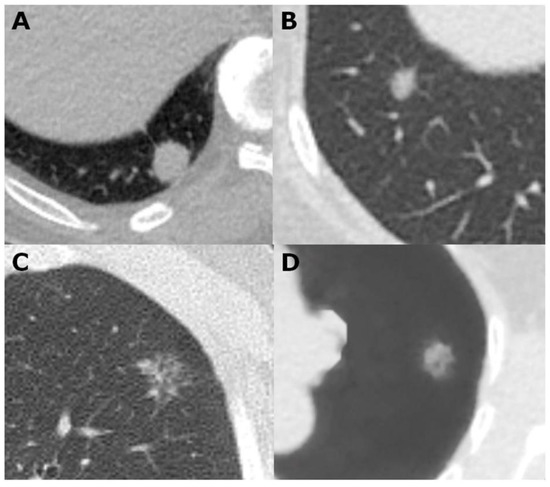

4.4. Lung-Nodule Characteristics and Images Interpretation

- Snoeckx, A.; Reyntiens, P.; Desbuquoit, D.; Spinhoven, M.J.; Van Schil, P.E.; Van Meerbeeck, J.P.; Parizel, P.M. Evaluation of the solitary pulmonary nodule: Size matters, but do not ignore the power of morphology. Insights Imaging 2017, 9, 73–86. [Google Scholar] [CrossRef]

- Kim, H.; Park, C.M.; Koh, J.M.; Lee, S.M.; Goo, J.M. Pulmonary subsolid nodules: What radiologists need to know about the imaging features and management strategy. Diagn. Interv. Radiol. 2013, 20, 47–57. [Google Scholar] [CrossRef]

- Fan, L.; Liu, S.-Y.; Li, Q.-C.; Yu, H.; Xiao, X.-S. Multidetector CT features of pulmonary focal ground-glass opacity: Differences between benign and malignant. Br. J. Radiol. 2012, 85, 897–904. [Google Scholar] [CrossRef]